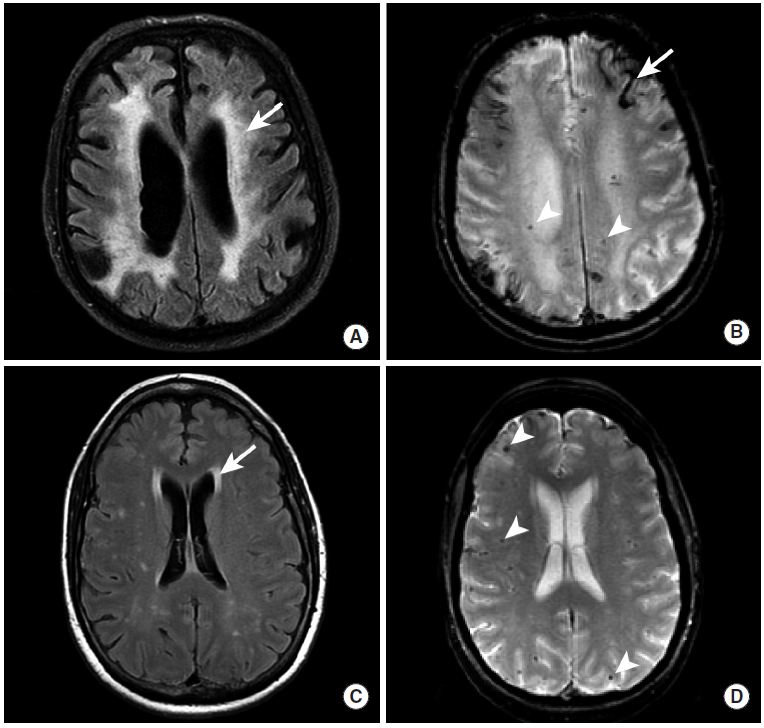

脑淀粉样血管病引起的脑实质出血

图8

本例患者的CT平扫(图A)、MRI的GRE(图B)和SWI(图C)序列显示右颞叶和枕叶的脑实质内出血(长尾箭头)。这种出血的典型表现是脑叶出血,并不限于动脉的供血区域。本例患者最终被诊断为脑淀粉样血管病。

图9

本图显示了两名脑淀粉样血管病患者的一系列MRI检查序列。

图A、B:本例患者的MRI的FLAIR序列中,整个脑白质区域表现出了弥漫性的高信号异常,即继发于动脉壁中淀粉状蛋白-β肽沉积的微血管病变(图A,长尾箭头)。 此外,皮层出血(图B,长尾箭头)和微出血灶(图B,三角箭头)显示为异常低信号。

图C、D:第二例患者的影像学检查中,脑白质异常不如前一例显著(图C,长尾箭头),但仍然存在数个微出血灶(图D,三角箭头)。